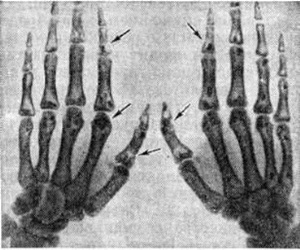

Такая патология в основной своей части характеризуется симметричным повреждением. Костные структуры скелета при остеопойкилозе на трентгенснимках визуализируется в структура с пятнистым окрашиванием, что и привело к такому названию патологии.

Рентгенографическое обследование позволяет диагностировать патологическое состояние. На снимках достаточно легко визуализируются плотноватые округлые образования до 0,8 см. В некоторых случаях они подобны полоскам толщиной до двух миллиметров и длиной до десяти. Смешанная форма патологического процесса наблюдается в исключительных случаях. Причем внешние признаки костных структур совершенно не изменены, а ядра оссификации образуются своевременно, и им характерна вполне нормальная структура.

- стопах, кистях (частым местом поражения являются короткие губчатые кости конечностей);